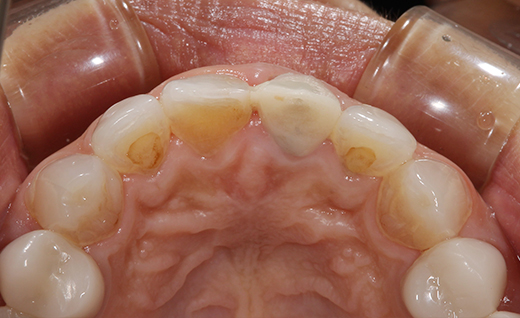

施術前

前歯の保険適応の被せものの変色や、歯の色が自然でないと感じておられ、今回オールセラミックへ変更させていただきました。